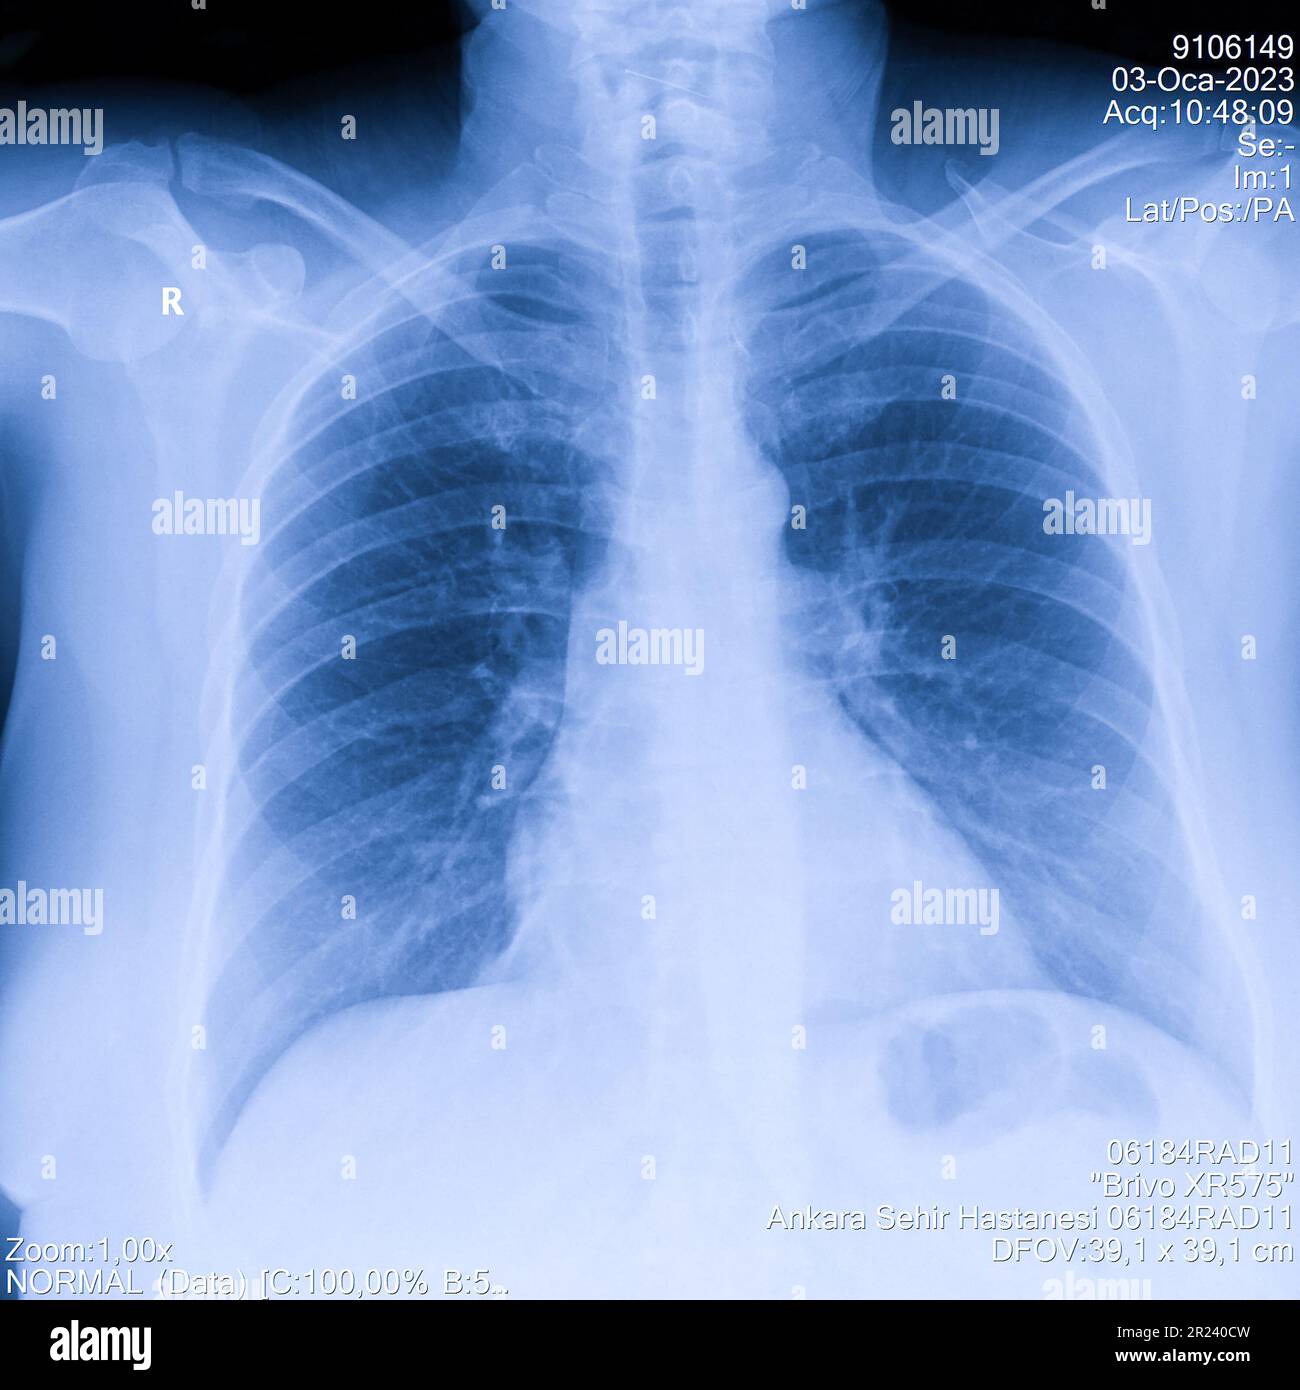

Lung Cancer Screening X Ray

Experience the clarity of Lung Cancer Screening X Ray with our curated collection of comprehensive galleries of images. featuring understated examples of photography, images, and pictures. designed to emphasize clarity and focus. Discover high-resolution Lung Cancer Screening X Ray images optimized for various applications. Suitable for various applications including web design, social media, personal projects, and digital content creation All Lung Cancer Screening X Ray images are available in high resolution with professional-grade quality, optimized for both digital and print applications, and include comprehensive metadata for easy organization and usage. Our Lung Cancer Screening X Ray gallery offers diverse visual resources to bring your ideas to life. Comprehensive tagging systems facilitate quick discovery of relevant Lung Cancer Screening X Ray content. Multiple resolution options ensure optimal performance across different platforms and applications. Time-saving browsing features help users locate ideal Lung Cancer Screening X Ray images quickly. The Lung Cancer Screening X Ray archive serves professionals, educators, and creatives across diverse industries. Instant download capabilities enable immediate access to chosen Lung Cancer Screening X Ray images. Whether for commercial projects or personal use, our Lung Cancer Screening X Ray collection delivers consistent excellence. Professional licensing options accommodate both commercial and educational usage requirements.